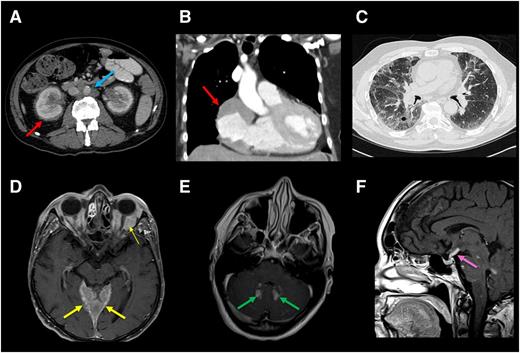

Radiographic findings of internal organ systems commonly affected by ECD. (A) Axial CT scan of abdomen of an ECD patient demonstrating dense infiltration of perinephric fat commonly seen in ECD and referred to as a “hairy kidney” appearance (red arrow). Circumferential soft-tissue sheathing of the thoracic aorta seen in a subset of ECD patients and referred to as a “coated aorta” (blue arrow). Right atrial mass is demonstrated in B. (C) Lung parenchymal infiltration on chest CT in an ECD patient. Axial postgadolinium T1 MRI in (D) demonstrates expansile enhancement of the pachymeninges (thick arrow) as well as orbital masses (thin arrow) and (E) enhancing lesions in the dentate nuclei of the cerebellum. (F) Sagittal postgadolinium T1 MRI shows thickening and enhancement of the pituitary stalk.

Cardiovascular involvement is common but frequently asymptomatic and detected incidentally by CT or MRI.34,35 The most common abnormality is circumferential soft-tissue sheathing of the thoracic and abdominal aorta and its branches visualized on CT scan, the so-called “coated aorta,” present in up to two-thirds of patients (Figure 2A).15,36 If renal arteries are involved, renovascular hypertension may develop and ultimately require stenting. Coronary arterial disease resulting in myocardial infarction has been described.36-38 Pericardial disease occurs in 40% to 45% of patients and can present with pericarditis, effusion, and even tamponade.32,39,40 Mural pseudo-tumoral infiltration of the right atrium is present in up to one-third of patients, visualized clearly on MRI as a mass lesion (Figure 2B), rarely causing valvular dysfunction and conduction abnormalities.34,35 Diffuse infiltration of the myocardium or interatrial septum has been described, occasionally leading to heart failure.41,42 Involvement of intrahepatic veins causing portal hypertension as well as the mesenteric vessels leading to ischemia have been seen but not published.

Radiographic lung involvement may be present in up to one-half of cases, involving either the lung parenchyma or the pleura (Figure 2C).15,43 Plain films are typically normal, but high-resolution CT may demonstrate interlobular septal thickening, ground-glass opacities, or centrilobular opacities.22 Frank consolidations are uncommon. Fluid from bronchoalveolar lavage, if performed, may contain macrophages and foamy histiocytes. Pulmonary involvement is often asymptomatic but can rarely manifest as cough or dyspnea. Spirometry may demonstrate restrictive features and decreased diffusion capacity.

The frequency of central nervous system (CNS) involvement in ECD varies from 25% to 50%.22,44 Parenchymal CNS lesions are a significant cause of functional disability in ECD and have been found in one series to be an independent predictor of death.45 Infiltrations can occur throughout the neuraxis, both in the intra-axial and extra-axial compartments. Expansile, gadolinium-enhancing lesions of the pachymeninges can occur overlying the cerebral hemispheres or in the cerebellar tentorium (Figure 2D). They can appear similar to meningiomas, granulomatous diseases, or meningeal infiltration by Rosai-Dorfman disease or LCH.32,33 Lesions present with focal symptoms referable to compression of local structures or, when disease is diffuse and bulky, with generalized deterioration of cognition and gait. Intra-axially, ECD manifests more commonly in the dentate nuclei of the cerebellum or in the pons, causing progressive cerebellar symptoms such as ataxia and dysarthria as well as brainstem symptoms (Figure 2E).22,25,46 These abnormalities tend to be gadolinium-enhancing and may be mistaken for primary or metastatic tumors, demyelinating disease, inflammatory processes, or leukodystrophies.28,29 Similar intracranial lesions have been reported in JXG.47 Infiltrative CNS lesions in LCH have similar distribution and radiographic appearances to lesions in ECD, with the exception of meningeal lesions, which are more expansile in ECD, and the spinal cord, which is spared in LCH. A degenerative atrophic process in the posterior fossa is an uncommon but well-described manifestation of LCH48 ; neurodegenerative phenomena in ECD remain uncharacterized.

Unilateral or bilateral infiltration of the orbits occurs in ∼25% of patients and can present as exophthalmos, retro-orbital pain, oculomotor palsies, or blindness.15,49 These pseudotumoral lesions have a differential diagnosis that includes Graves disease, granulomatous disease, lymphoma, and giant cell arteritis.

Diabetes insipidus is a shared feature of ECD and LCH, occurring in ∼25% of ECD patients, although several endocrinopathies have been reported, including hyperprolactinemia, gonadotropin insufficiency, and hypotestosteronism.15 Radiographically, the pituitary gland, stalk, and hypothalamus may be normal; alternatively, enlargement and abnormal enhancement of these structures can be appreciated on MRI with or without accompanying endocrinopathy (Figure 2F).50

Infiltration of perinephric tissues leading to the “hairy kidney” is common, as is hydronephrosis and ureteral narrowing (Figure 2A). Furthermore, ∼30% ECD patients present with imaging features suggestive of retroperitoneal fibrosis; however, unlike idiopathic retroperitoneal fibrosis, the pelvic ureters and inferior vena cavae are typically spared.15 Ureteral stenting or even nephrostomy may be required if hydronephrosis is associated with renal insufficiency.